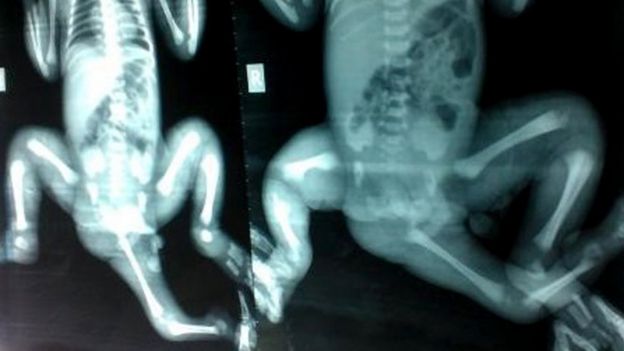

وتبلغ تشويتي خاتون من العمر 3 أعوام، وولدت برجل زائدة نمت في تجويف حوضها، وهو في الواقع جزء من جسم توأم لها لم يكتمل نموه.

وأوضح الدكتور كيمبر أن الأطباء في بنغلاديش "أزالوا جزءا من الرجل الزائدة، ولكن الجزء الأكبر بقي في منطقة الحوض بين رجليها الطبيعيتين".

ونمت في حوض الطفلة أعضاء أخرى للتوأم غير المكتمل، وبعد فترة طويلة من التحضير، باشر فريق الأطباء إجراء العملية في نوفمبر/ تشرين الثاني.

فأزالوا الجزء الباقي من الرجل الزائدة ثم شرعوا في ترميم الحوض، لتتمكن الطفلة من العيش بطريقة طبيعية.